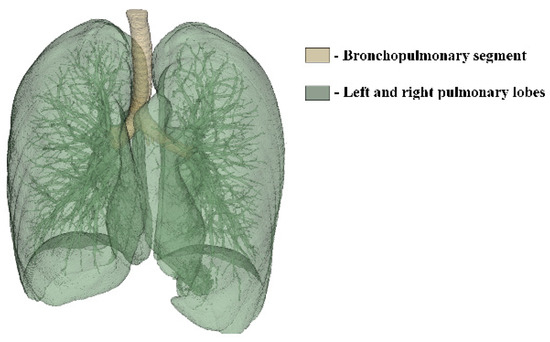

To generate a 3D model of the lower respiratory tract, CT images of the lungs were loaded into the 3D Slicer program and displayed in three projections. Figure 6 shows the result of the automatic generation of a 3D lung model.

The automatic generation of the lungs’ 3D model from CT images resulted in the amalgamation of the bronchopulmonary trunk and pulmonary lobes into a singular 3D model, lacking the capability to differentiate between them. However, for the subsequent modeling of drug dispersion within the lower respiratory tract, isolating the bronchopulmonary trunk becomes imperative. Hence, CT images, loaded in three projections, underwent layer-by-layer processing using the Segment Editor toolkit in the 3D Slicer program. This meticulous process of identifying the free volume of the airways enabled the generation of a distinct 3D model representing the bronchopulmonary trunk. The outcome of processing the CT lung images and the resulting 3D model are depicted in Figure 7.

Figure 6. Automatically generated 3D model of the lungs in the 3D Slicer program.